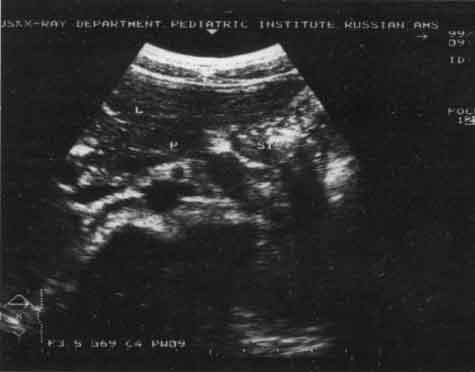

Рис. 7. Эхограмма прямой и сигмовидной кишки (продольный срез) при гипотонусе.

Рис. 8. Эхограмма прямой и сигмовидной кишки (продольный срез) при гипертонусе.